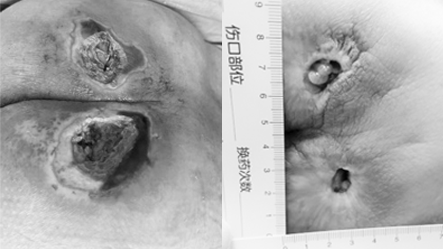

高龄的王大爷(化名)因脊髓外伤 + 帕金森病长期卧床,臀部压疮从 Ⅱ 期拖成 IV 期,肌层腐烂伴感染,辗转求医无果后,在昆山市中医医院急诊外科创面修复团队的救治下,靠改良中医古方,仅用两个月就重获健康肌肤。

起初家属发现他臀部皮肤发红破损,确诊为 Ⅱ 期压疮,可四处求医后治疗效果一直不佳。等转诊到昆山市中医医院时,创面已经腐烂深及肌层,还伴着感染渗脓,发展成了 IV 期压疮。

在团队的精准治疗和家属的细心护理下,王大爷的创面一天天好转:

• 换药1周后,感染得到控制,渗脓明显减少;

• 1个月后,

腐烂组织逐渐脱落,新鲜肉芽开始冒出;

• 两个月后,创面完全愈合,肉芽组织红润饱满,王大爷终于能安心翻身、坐起,不再受剧痛折磨。